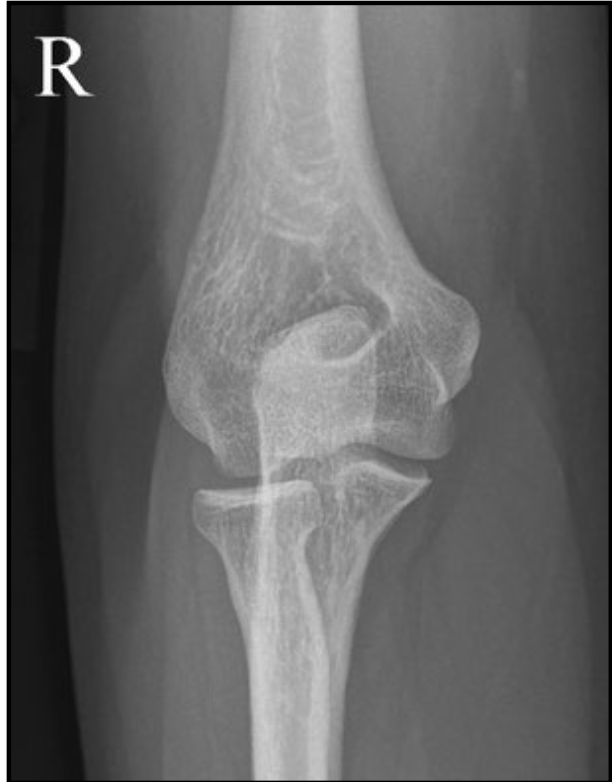

AP elbow criteria

A

Medial and lateral humeral epicondyles

are in profile

* 1/4” overlap of radial head on ulna

* 50% of the radius at the radial

tuberosity is superimposed by the ulna

* Capitulum-radial joint space is open

↳have all 3 jointson same plane

* Radius and ulna are parallel